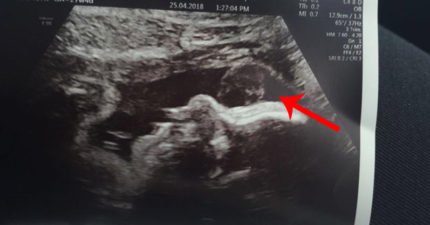

準媽媽超音波照驚現「靈異亮點」!她噴淚:感覺到在我身邊

April 30, 2018

世界, 圖文